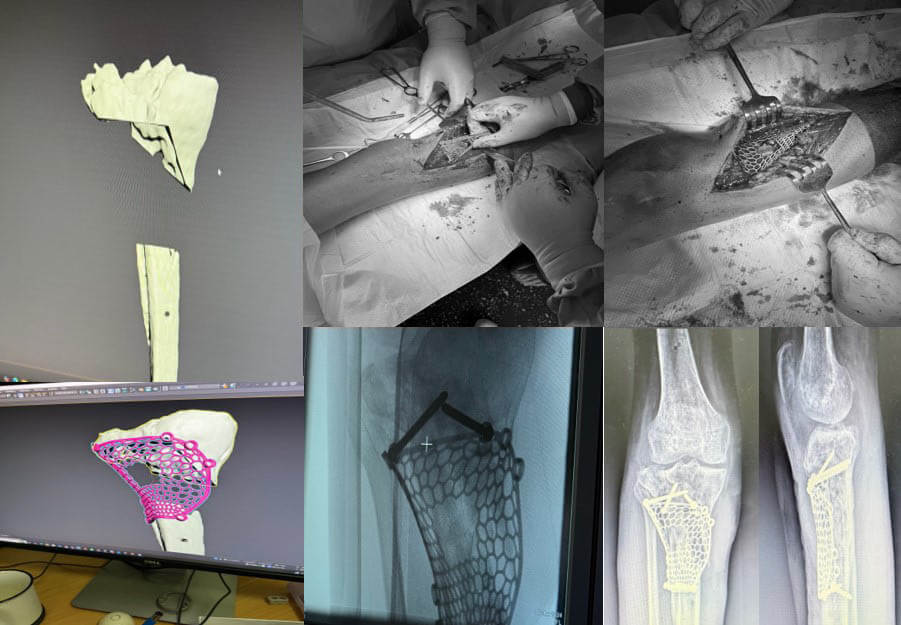

В лабораторії Біомедичної інженерії ІТО НАМН України виконано проектування індивідуального аугменту.

Етапи проектування індивідуальних аугументів для ревізійного ендопротезування колінного суглоба

Паціент М., Міно-вибухове поранення кісток колінного суглобу. Мегадефекти стегнової та Великогомілкової кістки 3 ст по класифікації (Aori). остіоміеліт. Стан після заміщення дефектів спейсером з антибіотиком

Виконане операційне втручання: Видалено спейсери з антибіотиком, резекція за допомогою індивідуальних навігаційних систем та імплантовано ендопротез з індивідуальними аугментами

Етапи проектування імплантатів при онкопротезуванні

Етапи онкологічного протезування